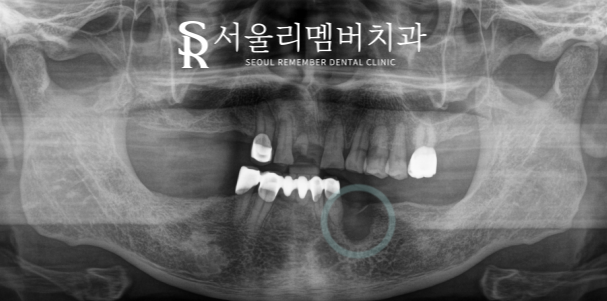

초진 파노라마 사진을 보면

이미 빠져 있는 치아들이 굉장히 많았습니다.

어금니 거의 대부분이 상실되어 있었으며,

광범위한 염증 및 치조골 소실로 인해

남아있는 치아들의 상황도 좋지 않았는데요.

환자분과 대화를 나눠보니

빠져버린 치아 때문에 제대로 된 식사도 하지 못하고

거울을 볼 때마다 손으로 가리게 된다고 하셨는데요.

기능적으로나 심미적으로나

문제가 많은 상황이었기에

하루빨리 개선을 도와드려야겠단 판단이 들었습니다.